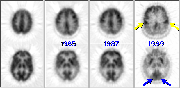

It now appears possible to diagnose Alzheimer's disease early in its course, noninvasively and reliably with PET. It has been over ten years since the first report from PET laboratories described decrements in cerebral blood flow, oxygen utilization and glucose metabolism in the parietal and temporal lobes of patients with Alzheimer's disease. Since that time, these findings have been extensively confirmed by numerous independent laboratories. The lack of any other clinical, biochemical or genetic marker for Alzheimer's disease during life makes these findings unique and of clinical relevance. We will now examine a series of PET scans taken from an Alzheimer's patient over a number of years.

Click on image above to view full-size image.For reference, the image on the left is an FDG-PET scan from a normal volunteer. The AD patient was first scanned in 1985, as shown above on the right. Note the decreased metabolic activity evident in the parietal (yellow arrows) and temporal (red arrows) lobes. Hypometabolism of the temporal and parietal cortices is common in mildly demented patients, and this profile appears to be indicative of the early stages of Alzheimer's disease. A large number of patients with signs and symptoms of dementia that have hypometabolism of the parietal and temporal lobes have had the diagnosis of Alzheimer's disease confirmed by biopsy or autopsy.

Click on image above to view full-size image.An FDG-PET scan of the same patient in 1987 re-confirms the metabolic deterioriation.

Click on image above to view full-size image.In the patient's 1989 FDG-PET scan, additional metabolic deterioration is apparent (Note: the 1989 images were acquired with a higher resolution scanner). The affected areas in the later stages of Alzheimer's disease typically include most regions of the cerebral cortex; particularly the parietal, temporal and frontal cortices (the frontal cortex typically becomes affected in later stages of the disease). There is relative sparing of primary sensorimotor cortex (yellow arrows), and of the primary visual cortex (blue arrows). In addition, phylogenetically more primitive subcortical structures of the brain are fairly well-preserved. This metabolic pattern is a distinguishing feature of Alzheimer's disease in neurological FDG-PET studies. Note that while structural imaging techniques such as MRI and CT are excellent in identifying the causes of dementia that have a structurally identifiable basis, PET imaging through metabolism has the ability to distinguish Alzheimer's disease from pseudodementia, Pick's disease, or early Huntington's as well as to identify individuals who have incidental cerebral infarctions superimposed on degenerative dementing processes.